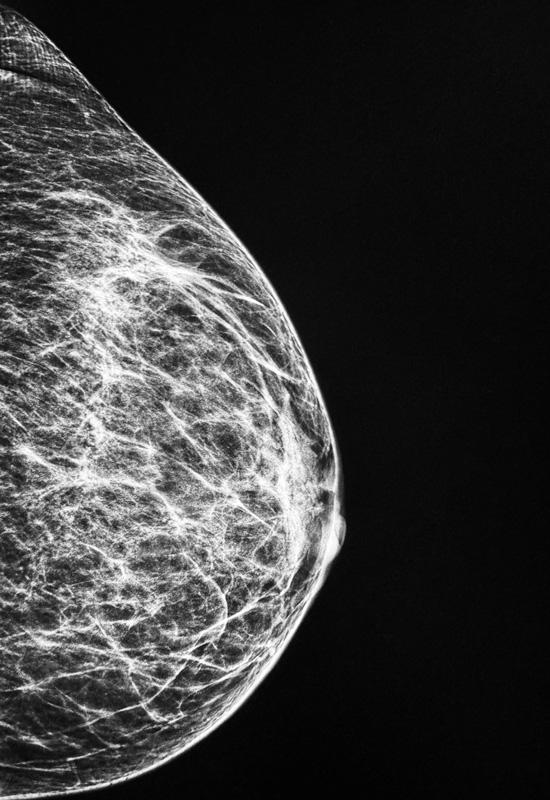

Brustultraschall / Mammasonographie

Der Brust-Ultraschall (Mammasonographie) dient der Untersuchung der Brust. Er wird zur Diagnostik von Gewebsveränderungen der Brustdrüsen angewandt.

Das Verfahren

Der Brust-Ultraschall (Mammasonographie) wird mit unhörbaren Ultraschallwellen durchgeführt, die sich vom normalen Schall durch eine andere Schwingungsfrequenz unterscheiden.

Bei der Untersuchung wird ein durchsichtiges Gel auf die Brust aufgetragen. Der Schallkopf wird mit sanftem Druck über die Brust bewegt. Bilder des Brustgewebes werden auf einen Bildschirm übertragen - das Untersuchungsergebnis liegt somit sofort vor.